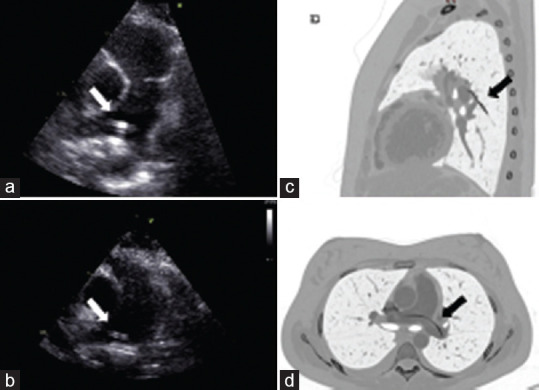

In the last few years, a tremendous advancement has been made in the therapeutical management of several diseases with an increasing need for parental drug administration. To avoid repeated venous insertions and the patient's anxiety related to these procedures, it is now common practice to insert a catheter to leave it in place for a longer time. However, these procedures may generate some complications, such as failure of insertion, embolization, and infection. Different noninvasive techniques have been proposed and used for the retrieval of lost or misplaced foreign objects. Here, we presented a case of the lost fragmented catheter in a young female who underwent a central venous catheter insertion 10 years ago, incidentally detected during an echocardiographic examination. Here, we presented a case of a lost fragmented catheter in a young female who underwent a central venous catheter insertion 10 years before.